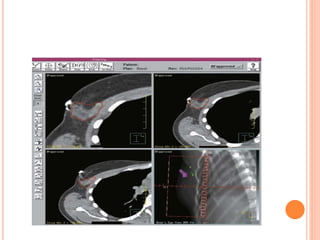

3D CRT AND RTOG GUIDELINES

PLANNING CT

 Take planning CT from

hyoid to cover marked

lower border

 3mm cut will be ideal

DURING CT SIMULATION

Post-BCS

Post-Mastectomy

REGIONAL NODAL CONTOURING

SCF begins

Axillary level III begins

Axillary level II begins

Axillary level I begins

Axillary level I ends

IMC begins

IMC ends